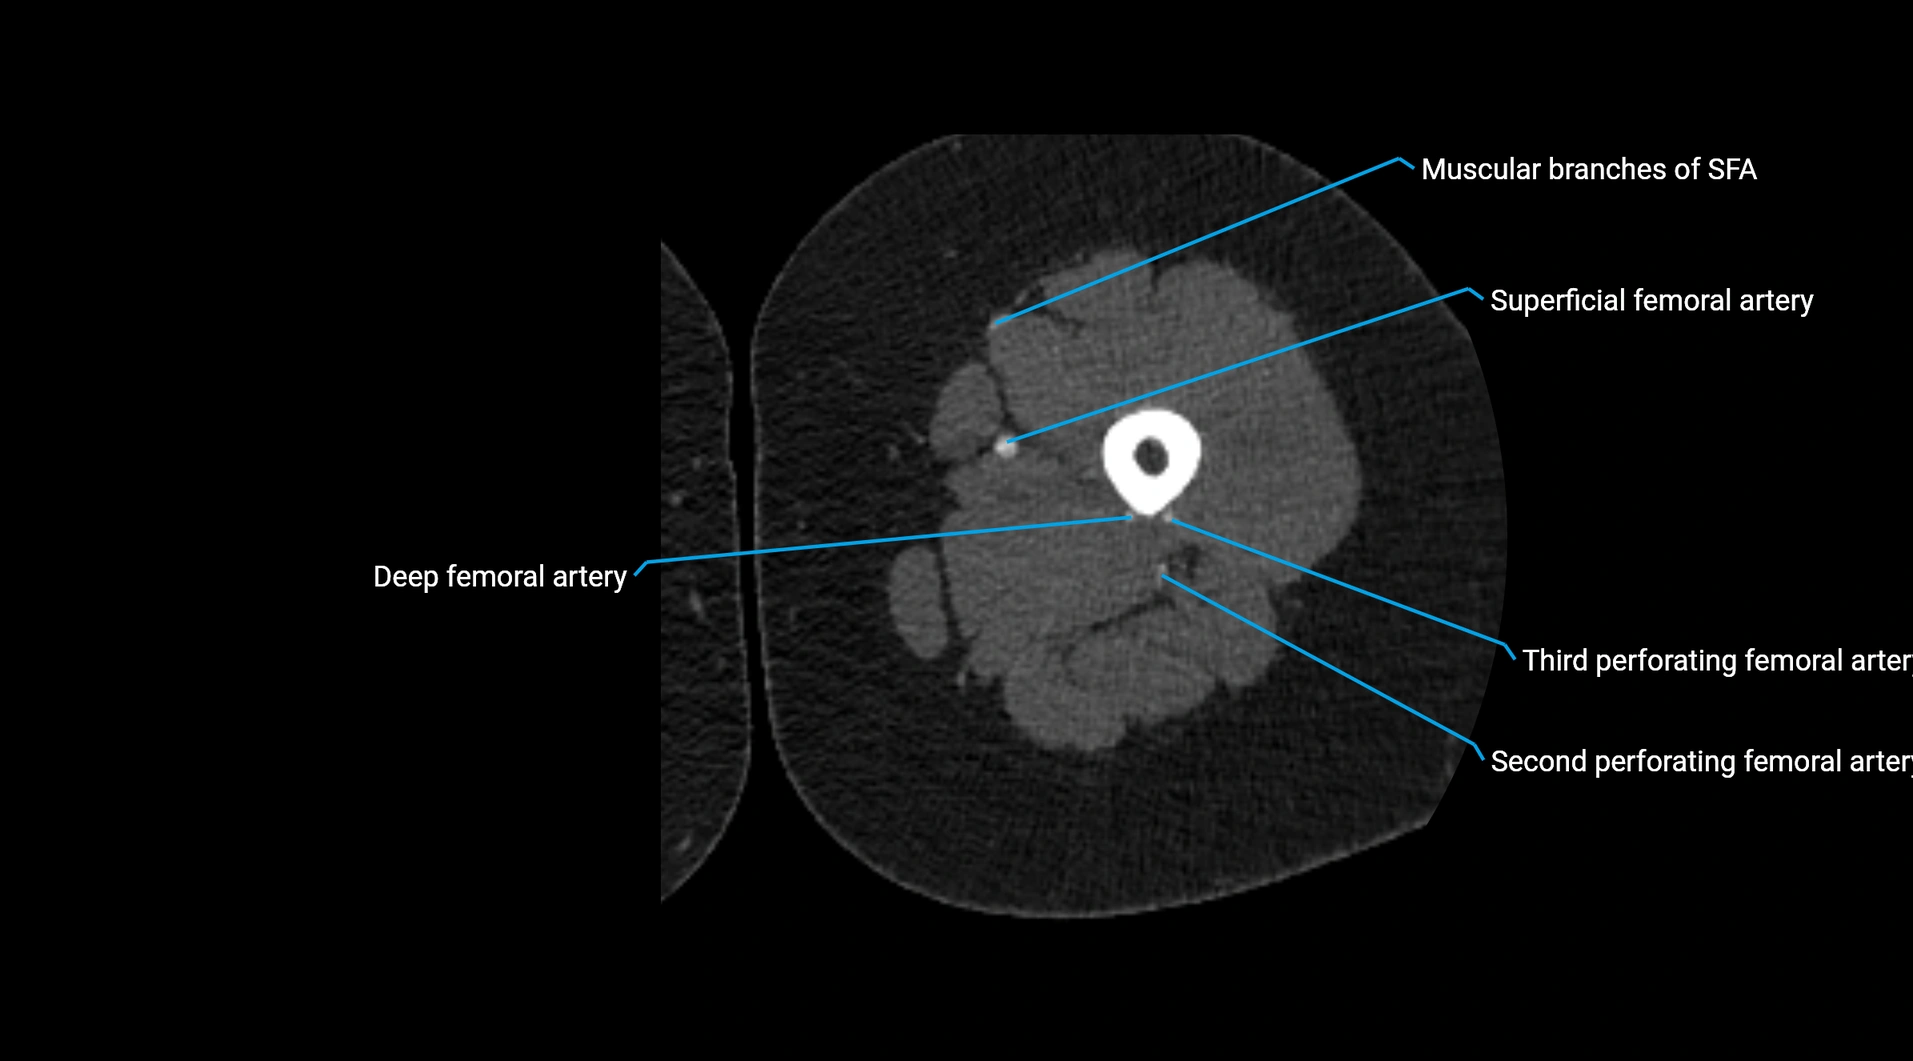

CT Appearance

Non-contrast CT:

• Appears as a tubular soft tissue structure anterior to vertebral bodies

• Calcified atherosclerotic plaques appear as hyperdense foci along the wall

• Useful for screening abdominal aortic aneurysm (AAA) size and mural calcification

Contrast-enhanced CT (CTA):

• Gold standard for abdominal aortic imaging

• Provides excellent detail of lumen, wall, aneurysm, thrombus, and branch vessels

• Multiplanar and 3D reconstructions help in aneurysm measurement, stent graft planning, and dissection evaluation

• Detects acute rupture, traumatic injury, or occlusion with high sensitivity